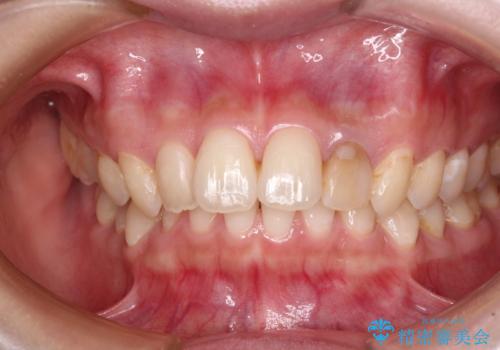

- 根管治療後に10年以上経過し、変色した前歯を気にして来院された患者様です。

根管治療はやり直さずに、ファイバーポストを使用した土台を植立してオールセラミッククラウンにて補綴することとしました。

神経を取り除いた歯は時間とともに変色してきます。

クリーニングやホワイトニングでは改善できないため、オールセラミッククラウンなどによる補綴治療が必要となります。